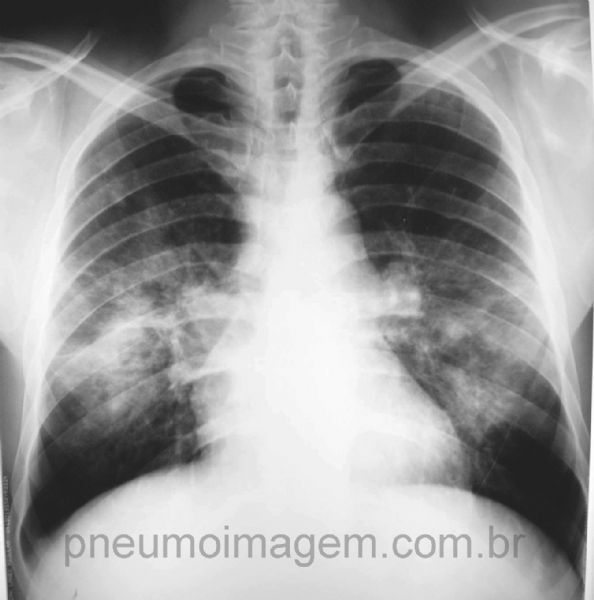

Esta imagem é sugestiva de que?

PARACOCCIOIDOMICOSE

Sintomas respiratórios arrastados lembrando TB (com este infiltrado)